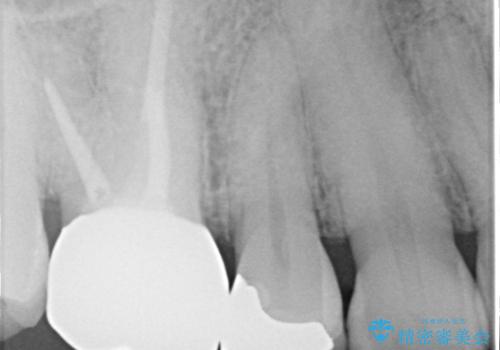

- 定期検診にてむし歯が見つかった患者さまです。

金属アレルギー体質とのことで、セラミックインレーにて修復治療を希望されました。

セラミックインレーは、金属やプラスチックに比べ汚れが着きづらく、むし歯の再発リスクを減らすことができます。